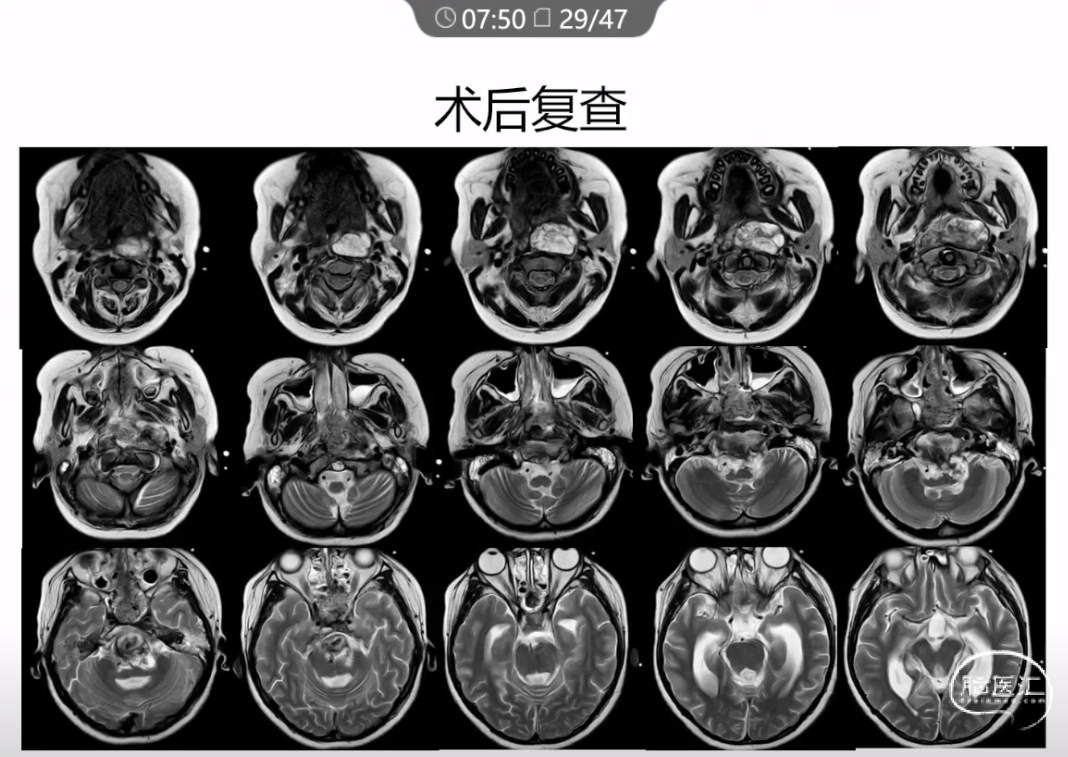

本文主要内容为:脊索瘤临床特点、治疗选择,以及多个手术病例。